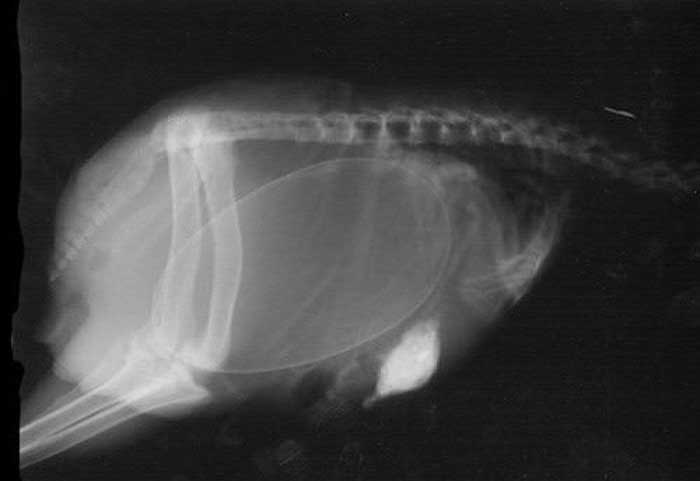

妊娠した様々な動物たちをレントゲン(X線)写真で見てみたギャラリー。サメ、ネズミ、犬、猫など。一度に複数の子供を出産する犬や猫などは特に怖い事に…。

8. モルモット(ネズミ)